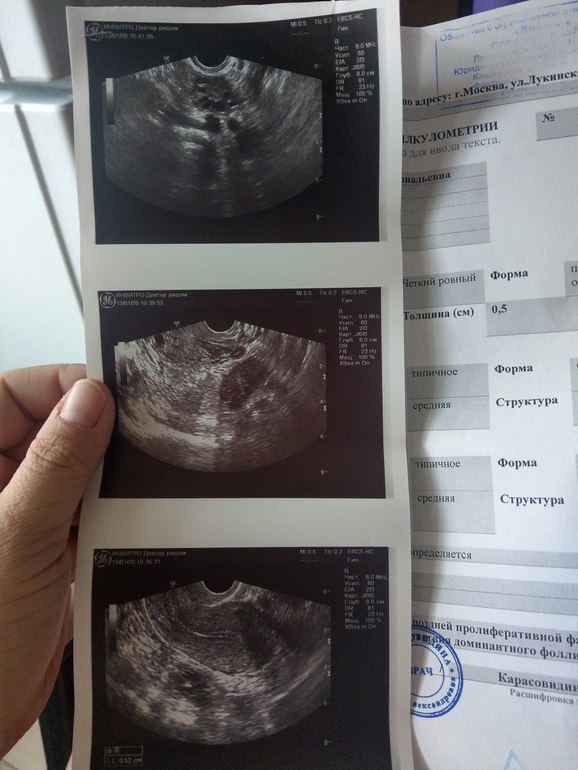

Позавчера я делала узи и по нему у меня эндик 5,2(допустим ладно) и совсем нет дф

переделала, жидкость в м тазу обнаружена и эндик изменился))

на этом узи врач не увидела даже яичник, вы писали в моем новом посте)

Да,она сказала все признаки овуляции (вот кроме пропавшего яичник)

не доминантные по прошлому узи были максимум 5-6 мм, просто не успели бы дорасти с понедельника

значит не увидели, как? одному богу известно

наверно в правом потерявшемся не увидели. хотя прошлая узистка якобы нашла его

реально была овуляция... только вот правый яичник в этот раз совсем не нашли. он совулировал судя по всему